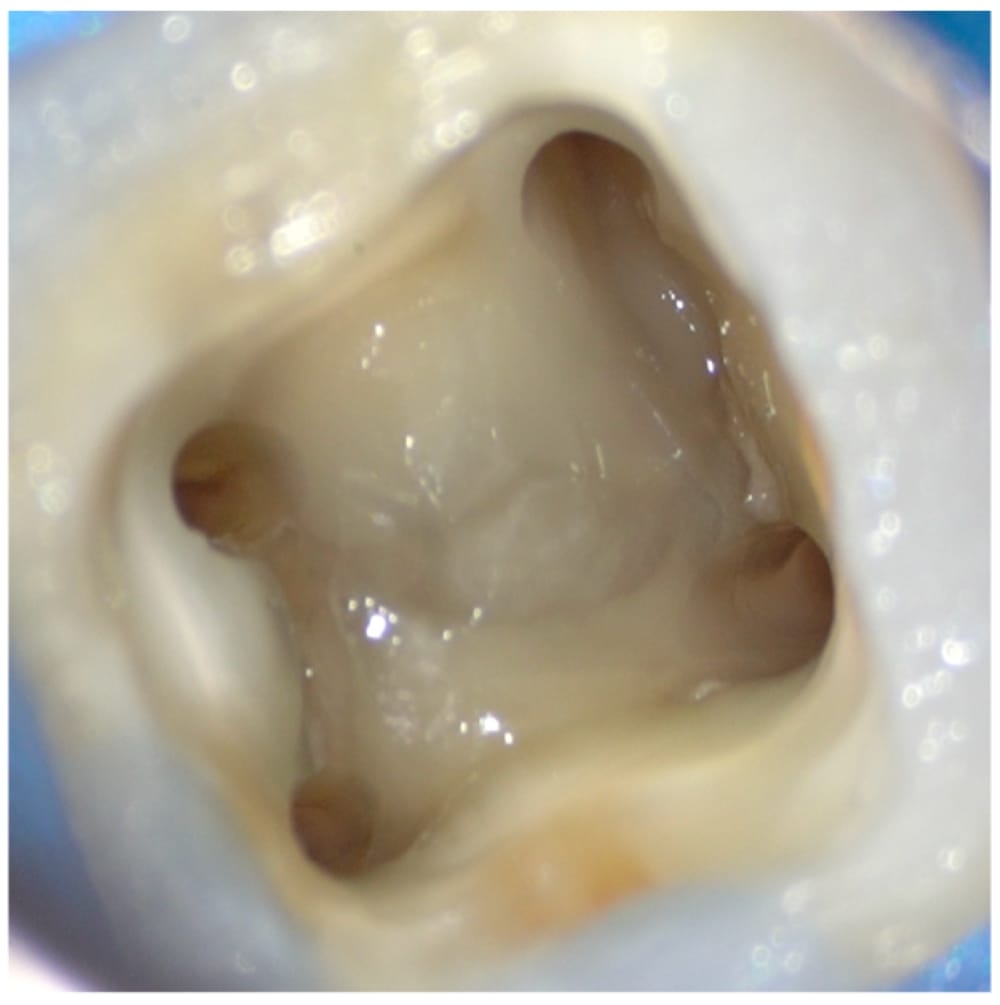

CTを撮影すると、根尖周囲に大きな骨吸収像が認められます。また、下顎第一大臼歯に一定の確率で発現するRadix Entomolarisという遠心舌側根が認められました。この根管は、通常の根管よりも湾曲が強く、治療の難易度が高いことから、より慎重に治療を進める必要がある状態であると術前の状態から判断できました。

4根管とも根尖まで穿通し、十分な細菌の除去を行ったのちに、根管充填を行い、レジンで封鎖し治療は完了しました。